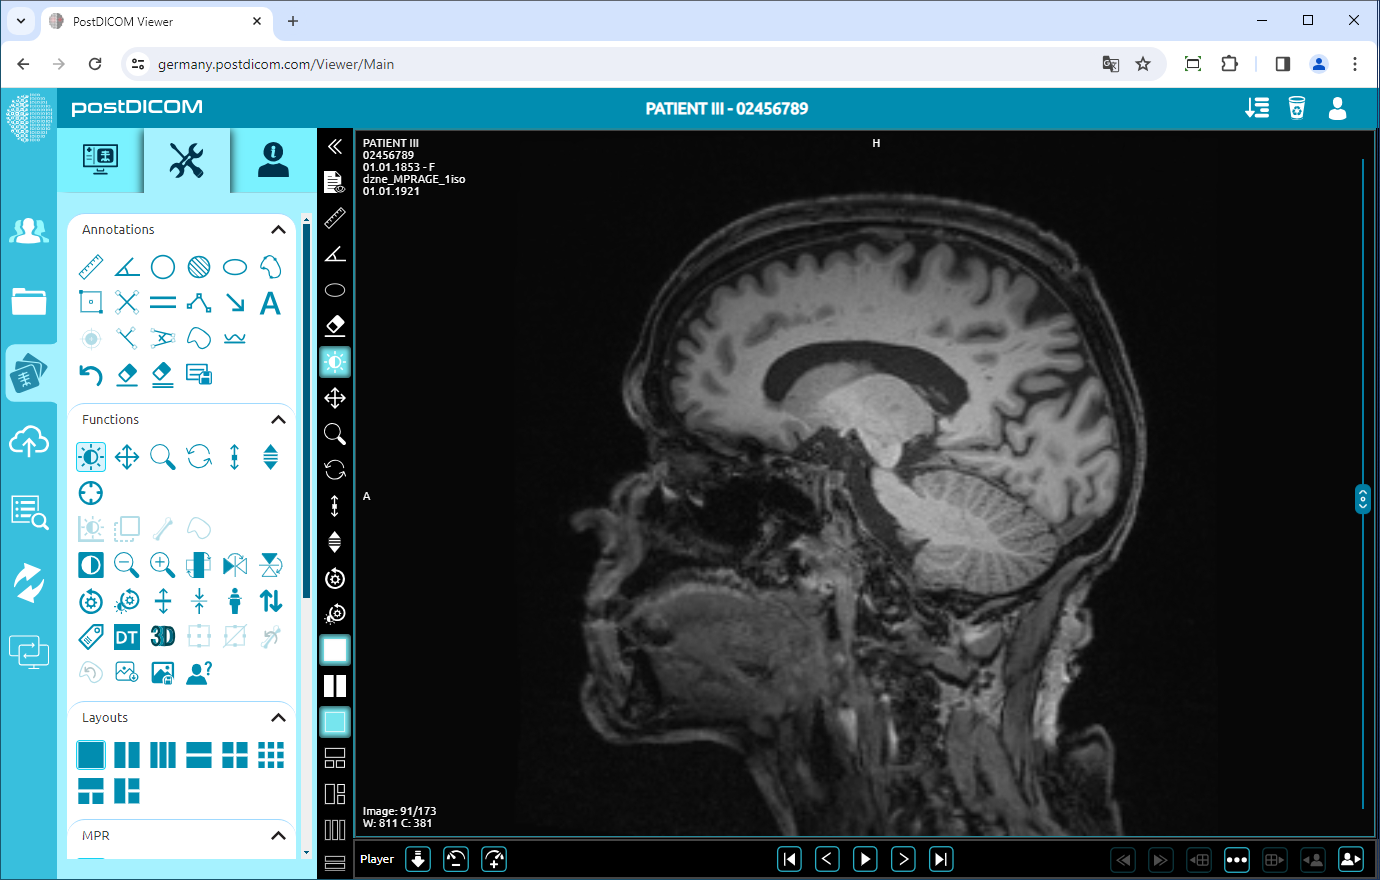

Rotate

Click on the “Rotate 90 Degrees” icon on the left side of the page.

If you click once, the image will rotate 90 degrees to the right. You can click twice to rotate the image 180 degrees, three times click to rotate it 270 degrees or four times click to rotate it 360 degrees (return to the original plane). The image rotated 90 degrees is shown below.